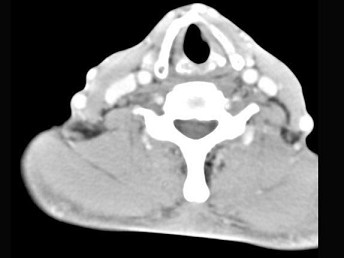

男,50岁,自觉咽喉部不适一个多月,间断刺激性咳嗽,CT扫描如图所示,正确的描述或诊断是 ( ) TJ-07321.jpg TJ-07322.jpg

• A.左侧声带内侧壁见结节状影向腔内突出,以宽基底与声带相连

• B.增强扫描结节强化不明显,密度均匀,周围结构未见受侵

• C.左侧声带息肉

• D.左侧声带乳头状瘤

• E.喉癌